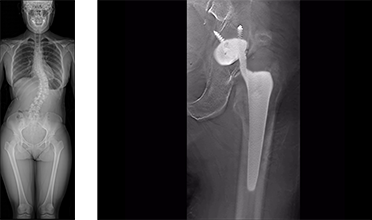

The bone density of lumbar vertebrae and femur bones can be measured by the DXA method, which is considered the most accurate way to measure bone mineral density using a fluoroscopy system.

*This option is only available in the Japanese market.

A variety of software applications are available for supporting radiography examinations, such as tomography software for confirming the fixation between artificial joints and bones and long-view radiography software for viewing large areas in a single image.